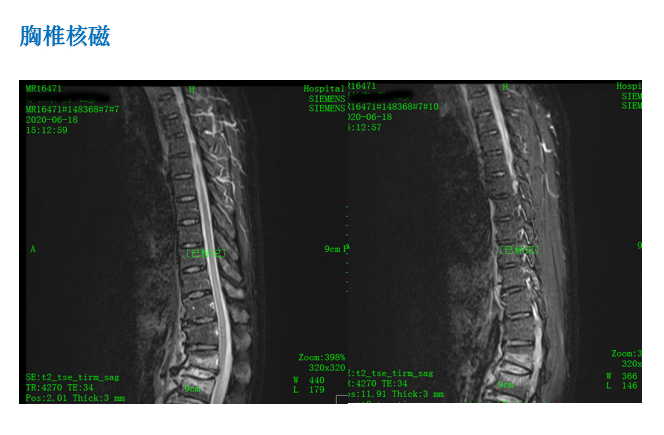

影像资料:

诊 断:

1:腰1、2椎体压缩骨折(椎体分别压缩约40%、10%);

2:腰椎退行性改变伴椎管狭窄;

3:腰3/4、4/5、腰5/骶1椎间盘膨出;

4:右跟骨骨折;

5:胸12陈旧性骨折。

治疗方案:

1:腰1、2椎体骨折复位内固定术,右跟骨骨折切开复位内固定术。

2:腰1、2椎体骨折复位内固定、腰3/4椎间盘摘除椎间融合内固定术,右跟骨骨折切开复位内固定术。

术后影像: